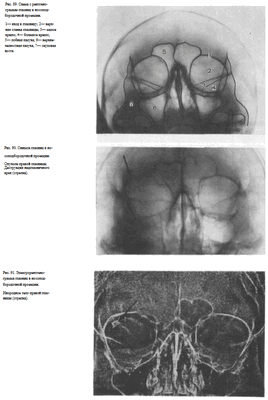

В качестве примера информативности снимка глазниц в носолобной проекции для выявления инородных тел глаза и деструктивных изменений стенок приводим два наблюдения.

Одно из них — случай ранения глаза металлической стружкой (рис. 93), другое — случай деструкции верхненаружного края глазницы при доброкачественной опухоли слезной железы (рис. 94).

Информативность снимка. На снимке хорошо видны вход в глазницу, структура ее стенок, иногда малое и большое крыло клиновидной кости (рис. 89). На снимке в этой проекции могут быть выявлены деструктивные изменения стенок глазницы и инородные тела в ее полости (рис. 90, 91). Для выявления изменений в области верхней стенки глазницы (например, при

диагностике переломов) снимок целесообразно выполнять не в носоподбородочной, а в подбородочной проекции.